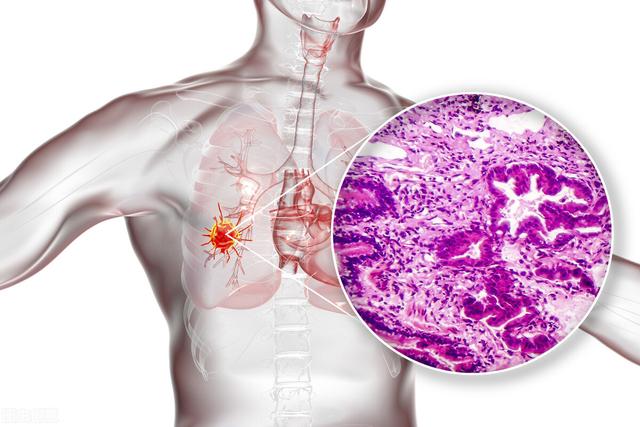

Hyperplasie adénomatoïde atypique du poumon → cancer du poumon

La Chine est aujourd'hui le premier pays touché par le cancer du poumon. L'hyperplasie adénomatoïde atypique dans les nodules pulmonaires fait partie des lésions précancéreuses. Parmi ces lésions, plus le nodule est gros, plus le risque de malignité est élevé.

D'après l'observation clinique de milliers de cas de nodules pulmonaires isolés, les nodules pulmonaires d'un diamètre inférieur à 0,5 centimètre ont une très faible probabilité de malignité, environ 1 % ; entre 0,5 et 1 centimètre, la probabilité de malignité est de 6 à 28 % ; la probabilité de malignité pour les nodules pulmonaires d'un diamètre de plus de 2 centimètres atteint 64 à 82 % ; et pour les nodules d'un diamètre de plus de 3 centimètres, 90 à 95 % des nodules pulmonaires sont malins.

Bien que l'incidence du cancer du poumon soit élevée, des examens médicaux opportuns permettent de détecter les nodules de cancer du poumon le plus tôt possible.Il est recommandé aux fumeurs de se soumettre à un dépistage annuel par tomodensitométrie hélicoïdale à faible dose pour détecter les premiers stades du cancer du poumon, et d'arrêter de fumer rapidement.